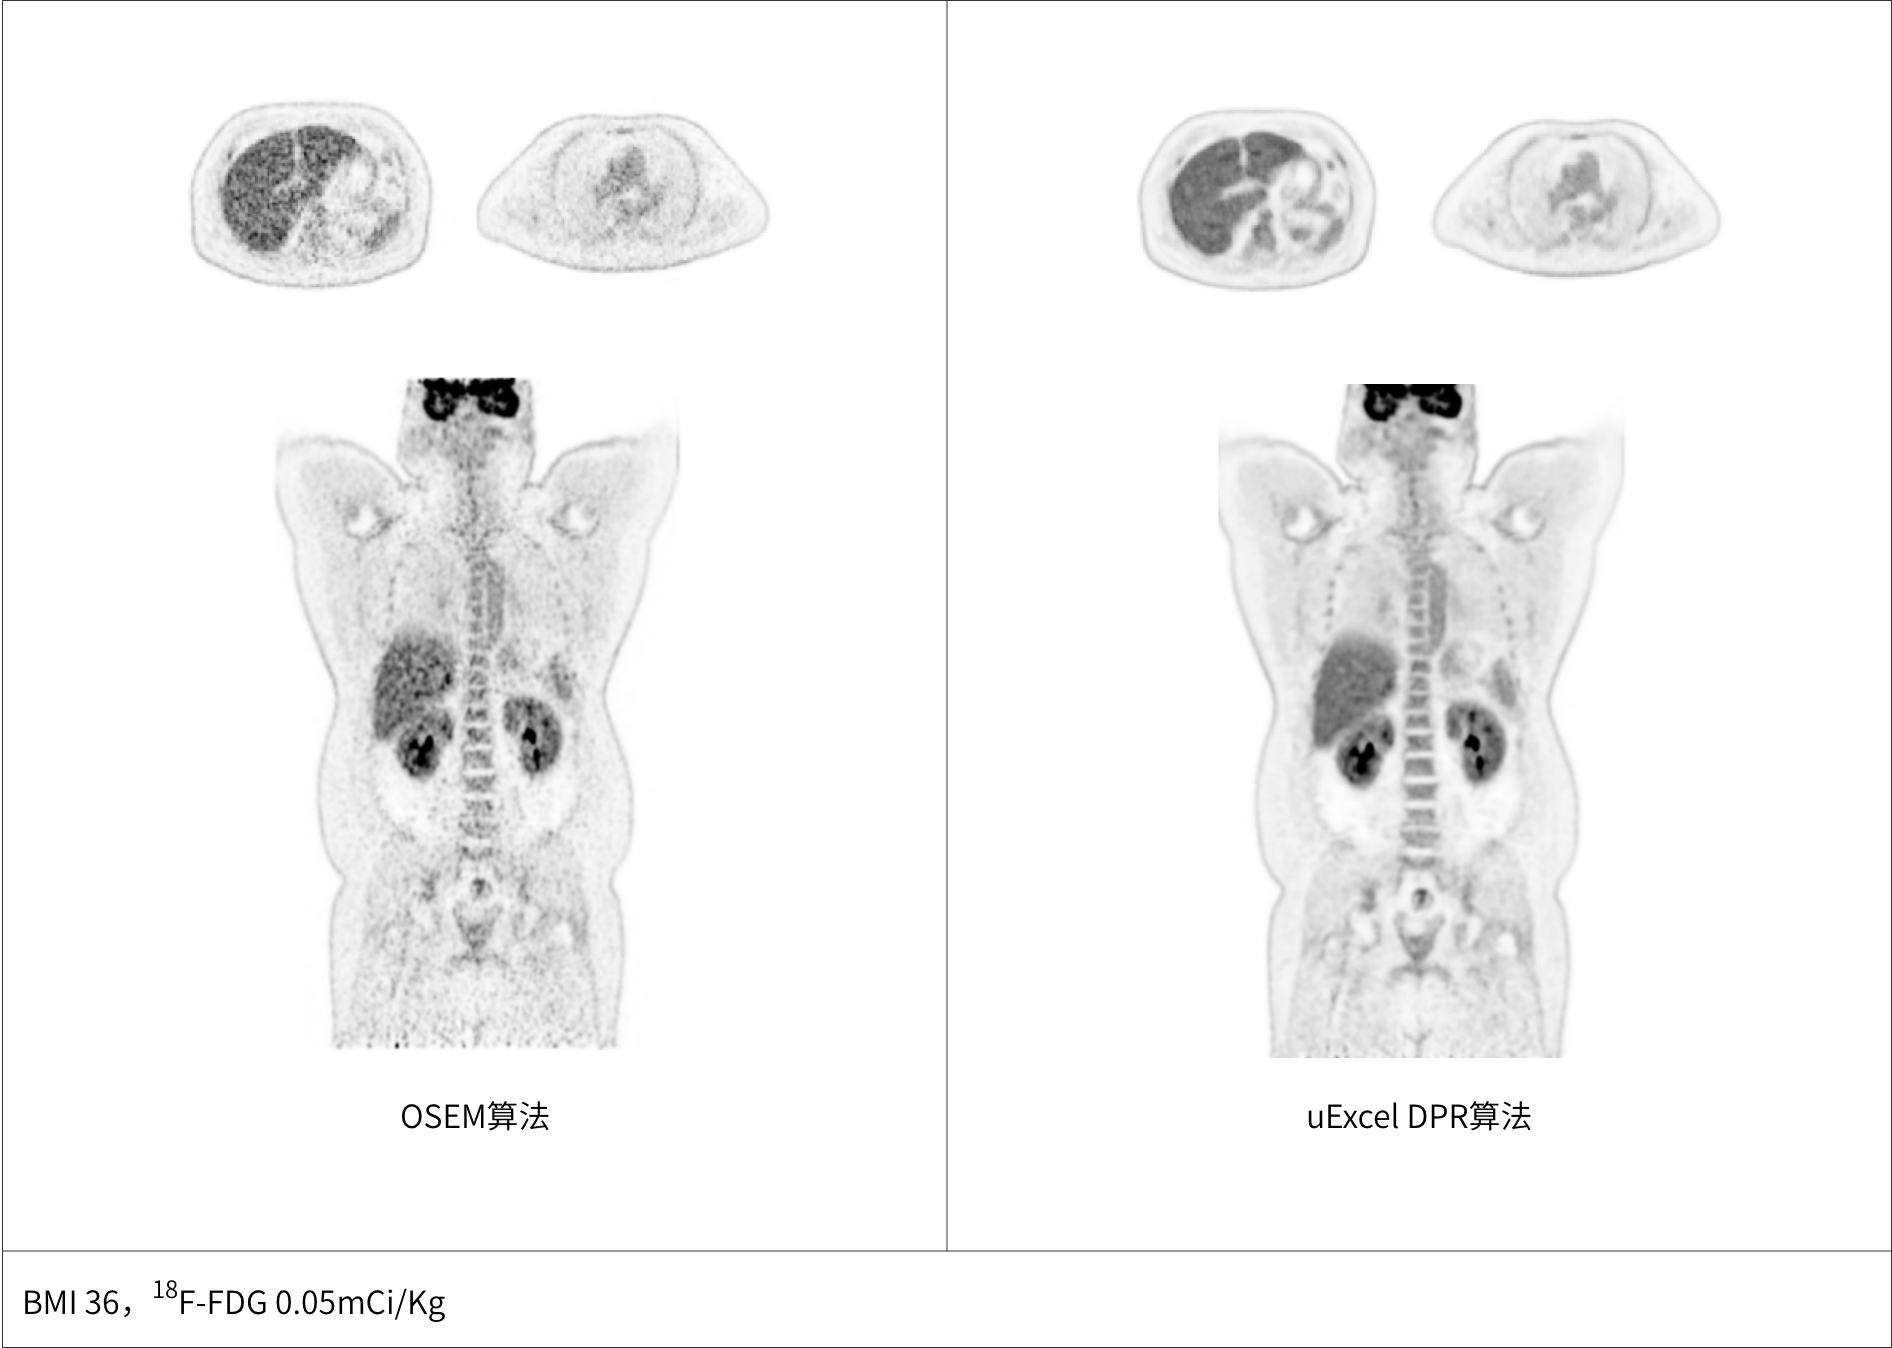

兼顾噪声、对比度、分辨率等多维度进行分布渐进式学习优化

极低噪声、高对比度uEXPLORER海量优质图像训练集有效保证输出结果的可靠性

同时实现图像对比度、噪声、信噪比三重优化

*uExcel DPR仅供科研使用

多个神经网络嵌入迭代重建中,加速图像收敛